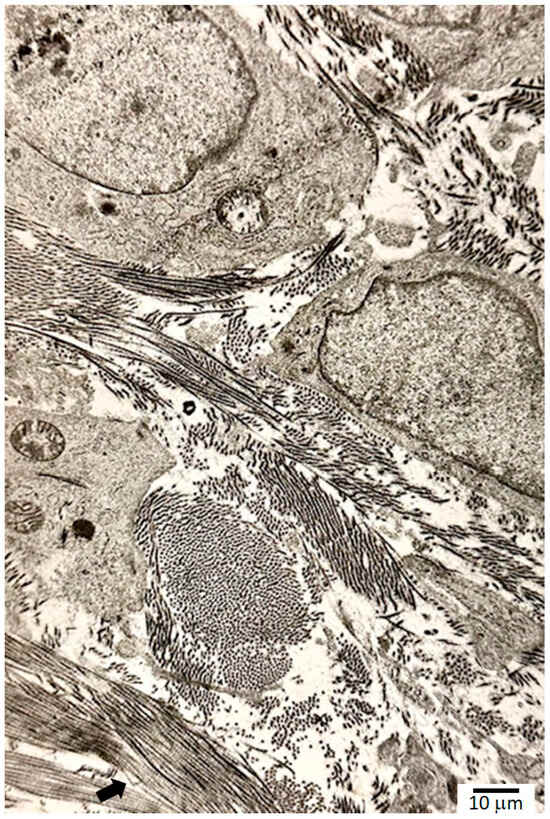

During the remodeling process, wound contracture occurs through the action of myofibroblasts. Myofibroblasts exert their contractile forces by focal adhesion complexes that link the intracellular elements such as the cytoskeleton to the ECM. Early scars appear pinkish red due to their dense capillary networks; regression of these capillaries allows scars to lighten significantly over time. Ultimately, the formation of a mature scar marks the end of the remodeling phase (Figure 3). In addition to a collagen pattern distinctly different from native skin, epidermal appendages such as pilosebaceous complexes are lacking in mature scars [45].

The histology of keloids shows dense, disorganized bundles of collage with an increase in fibroblasts. Immunohistochemistry of keloids reveals the presence of CD34−/α-SMA+/p16+ cells, in contrast to CD34+/α-SMA-p16- cells in the dermis of normal adjacent skin. Due to myofibroblasts, wounds of critical areas, such as the first webspace of the hand, the submandibular area of the neck, elbow, knee, axilla, and hip, undergo contraction and result in contractures which impede normal function by restricting both active and passive range of motion. Fibrosis is a major problem preventing full recovery after musculoskeletal surgeries. In 4% of the patients receiving breast implants, this manifests as contracture surrounding the implant [61].